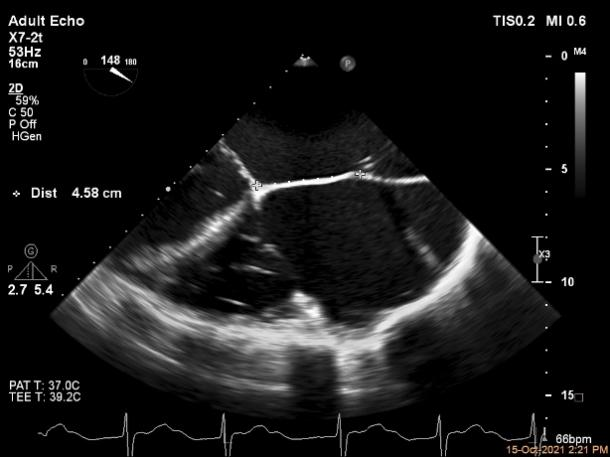

(1)本例中左房明显增大,目测类似常规患者的高度和距离,实际测量值发现位置其实已经很高或者较靠后,因此穿刺时位置应该稍低一些,略靠后。本例患者术中反复确认实际测量高度在4.5-5.0cm,再稍偏后位置进行了成功的房间隔穿刺。

(2)该患者双房明显扩大,空间结构出现了扭转,在Bi-Plane平面LVOT view看不到左室流出道,因此术中通过3D zoom将主动脉瓣旋转到12点钟方向 ,穿刺位置最好为3点钟,自内交界区上方较合适,确定穿刺高度后,左心房3D成像确认。因此,对于这类患者结合3D视图找到最合适的房间隔穿刺点是成功的关键。